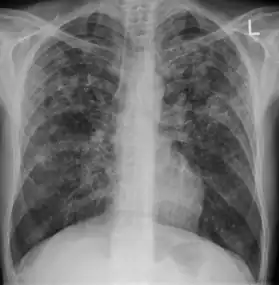

2. Any cavitary lesion - Lucency (darkened area) within the lung parenchyma, with or without irregular margins that might be surrounded by an area of airspace consolidation or infiltrates, or by nodular or fibrotic (reticular) densities, or both. The walls surrounding the lucent area can be thick or thin. Calcification can exist around a cavity.

-

Chest X-ray of a person with advanced tuberculosis: Infection in both lungs is marked by white arrow-heads, and the formation of a cavity is marked by black arrows.